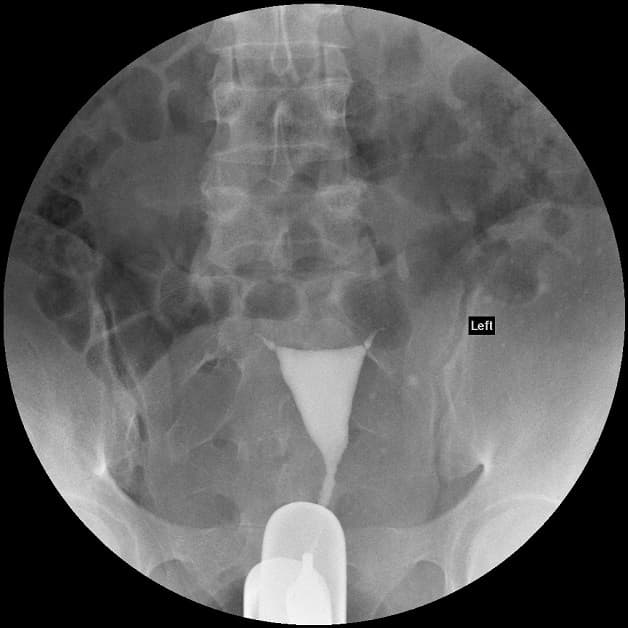

Chụp tử cung vòi trứng là kỹ thuật hiện đại nhằm chẩn đoán hình ảnh để quan sát sâu bên trong tử cung, vòi trứng và các cấu trúc ở xung quanh các bộ phận này. Phương pháp này thường được áp dụng ở những phụ nữ vô sinh hiếm muộn.

Khi chụp tử cung vòi trứng, người bệnh thường sẽ được tiêm thuốc cản quang bằng một ống nhỏ và đặt từ âm đạo đến tử cung.

Về cầu tạo, tử cung và vòi trứng thông nhau nên chất cản quang và chảy cả vào vòi trứng. Bác sĩ sẽ tiến hành chụp bằng cách sử dụng chùm bức xạ tia X khi bơm cản quang.

Hình ảnh chụp có thể cho thấy được các vấn đề, tổn thương hay bất thường ở bên trong cấu trúc tử cung, vòi trứng hoặc chỗ tắc nghẽn. Đây chính là nguyên nhân ngăn cản trứng đi qua để đến tử cung, ngăn cản tinh trùng di chuyển vào vòi trứng và thụ tinh.